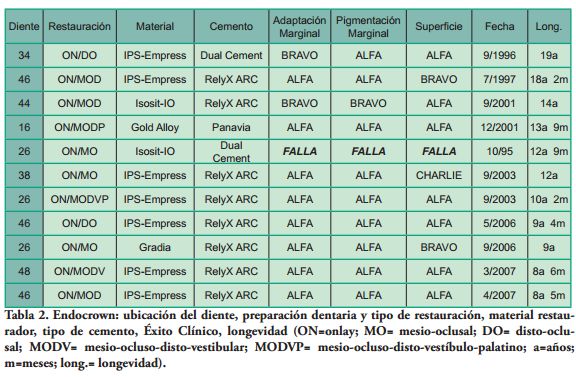

Adaptación Marginal, Pigmentación Marginal y Superficie, fueron las variables estudiadas para establecer la calidad de las restauraciones, siguiendo el criterio de Ryge, (16) modificado por los autores (Tabla 1).

Los Criterios de Éxito (CE) fueron definidos por los autores, de acuerdo al criterio de Ryge modificado y a lo establecido por Anusavice (17) y agrupados de la siguiente manera:

Tres materiales restauradores y tres cementos resinosos fueron utilizados.

Tres EC habían sido instalados en molares superiores, 5 en molares inferiores y 2 en premolares inferiores, observándose una relación 4.0 molares/premolares (Tabla 2).

Dos pequeñas fracturas en crestas marginales distales fueron pulidas, sin afectar la restauración. El Éxito Clínico, relacionado a la calidad de las restauraciones, fue Excelente, 5 (50%), Bueno, 4 (40%) y Sobrevida Funcional, 1(10%) (Tabla 2).

No existe evidencia científica suficiente respecto al comportamiento clínico de los Endocrowns. Estudios clínicos longitudinales de EC son escasos. Lander y Dietschi (7) presentaron 2 casos exitosos en 3 años; Biacchi y cols. (8) 1 caso en 3 años y Fages y Bennasar (9) un caso sin seguimiento. Después de un año, Otto (10) encontró que en 10 EC, la calificación de Bravo en Adaptación Marginal se incrementó de 30% a 55%. Por su parte, Bernhart y cols.(11), en 20 EC, en 2 años, tuvieron 90% de éxito. En el presente trabajo, 90.9% (10) EC permanecían en función con una sobrevida media observada de 12 años y 3 meses. Considerando la calidad de las restauraciones, el Éxito Clínico fue de 90%.